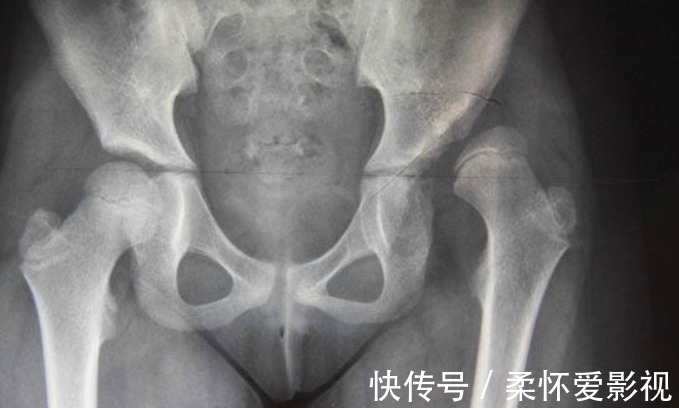

有个宝宝,走路时的姿态有点像鸭子般左摇右摆。家人没有在意。刚学走路,哪能那么稳当呢?大家把走路不稳归因于宝宝没有掌握好平衡。走了几个月,还是一点儿进步没有!体检的时候,问了一下医生,医生建议去儿童医院检查。结果出来了,先天性髋关节脱位。比较宽心的是,脱位角度比较小,矫正一段时间就可以。

5.患有先天性髋关节脱位这种疾病不容易发现,不痛不痒,只有仔细观察才会发现宝宝屁股两边不对称,双腿不愿意分开,走路时的姿势像鸭子般左摇右摆。先天性髋关节脱位是一种儿童四肢畸形的疾病,主要受遗传因素、子宫内机械性因素及婴儿的包裹方法等多项因素影响。肌肉张力下降,不能顺利爬行。脱位侧的下肢会显得比较短,走起路来一跛一跛的;即使情况最轻的,大腿皮肤纹理也会出现不对称的情况。 通过大动作异常,辨别宝宝疾病宝宝大动作异常可能预示着某种疾病,任何疾病都是早发现治愈可能性高,能减少疾病对宝宝的伤害。